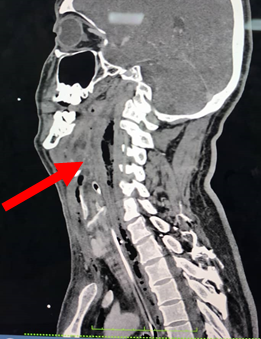

Retropharyngeal abscess is rare in adults that can lead to severe complications. We presented the case of a foreign patient developed a life-threatening retropharyngeal abscess, complicated with language barriers and a missed migrating chicken bone. A 42-year-old foreigner man with unknown comorbid presented with upper airway obstruction in a day, and neck swelling for 5 days. History taking was difficult due to a language barrier. The patient’s friend claims he experiencing sore throat, dysphagia and odynophagia for the preceding week. Examination showed biphasic stridor and diffused anterior neck swelling 5x5 cm, erythematous and warm. Flexible scope noted oedematous airway. Blood investigations showed sepsis. Patient intubated and urgent computed tomograpgy (CT) scan of the neck reported as extensive retropharyngeal collection. He underwent surgical drainage but the condition did not improve. Repeated CT scan revealed a migrating linear hyperdense foreign body at the C2/C3 level which was removed succesfully. Retropharyngeal abscess is a life-threatening condition with foreign body as a causative factor is uncommon in adults and can be challenging to detect, especially in the context of language barriers, thorough history taking, aided by imaging to locate the source of infection, led to the correct diagnosis and treatment.

Initial computed tomograpgy neck showed extensive multiloculated gas containing collection seen at retropharyngeal region (red arrow) from the level of oropharynx in sagittal section